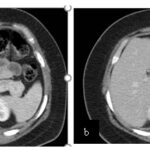

Se le practica una duodeno pancreatectomía cefálica y triple anastomosis (hepato yeyuno, gastroentero y wirsung enteroanastomosis) el 12 de octubre de 2023 y pasa a internación UTI, el 14 de octubre se complica con fiebre, dolor abdominal y fístula pancreática con dosaje de amilasa de drenaje >6000, por lo que se le realiza tomografía que muestra abundante líquido libre en cavidad. Por tal motivo se le realiza una exploración quirúrgica por laparotomía, encontrándose abundante líquido + pancreatitis en la anastomosis yeyuno pancreática. Se realiza lavado de cavidad + 3 drenajes abocados a zona pancreática + yeyunostomia.

Paciente que se intuba y pasa a UTI, posteriormente extubación exitosa. El 22 de octubre se complica con colección abdominal, por lo cual requiere de drenaje percutáneo guiado por TC.

Tomografía de abdomen y pelvis con cte ev: del 13/10/2023.

Complicaciones posquirúrgicas

Tomografía de abdomen con cte ev: del 20/10/2023.

Tomografía de abdomen con cte ev: del 26/10/2023.